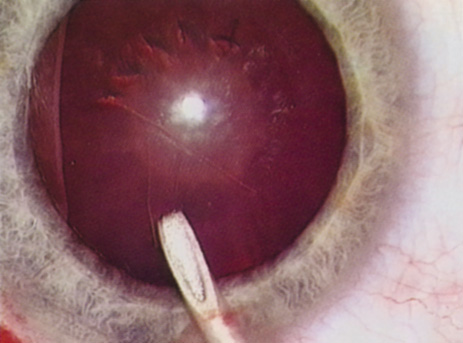

Fig. 10. The capsulorrhexis tear is more easily redirected by folding the capsule over, in advance of the tear.

Capsulorrhexis can be performed with a cystitome, capsulorrhexis forceps, or combination-type instruments. Regardless of which instrument is used, several principles can help the surgeon successfully complete capsulorrhexis. It is important to maintain the anterior chamber, because making the chamber shallow increases tension on the zonules and causes the tear to run peripherally. The authors recommend the use of a viscoelastic agent for maintaining chamber depth and, of course, for endothelial protection. Therefore, if the tear begins to run peripherally, the surgeon should redeepen the anterior chamber before attempting to redirect the tear. Additionally, folding the capsule margin can aid the surgeon in redirecting the tear more accurately (Fig. 10).